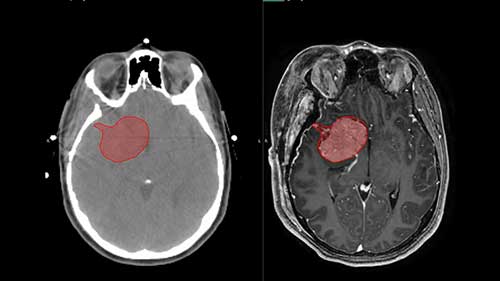

伽马刀放射外科手术详解

医学博士讨论了什么是伽玛刀放射外科手术,以及如何在不出现传统切口的情况下使用伽玛刀治疗脑肿瘤。